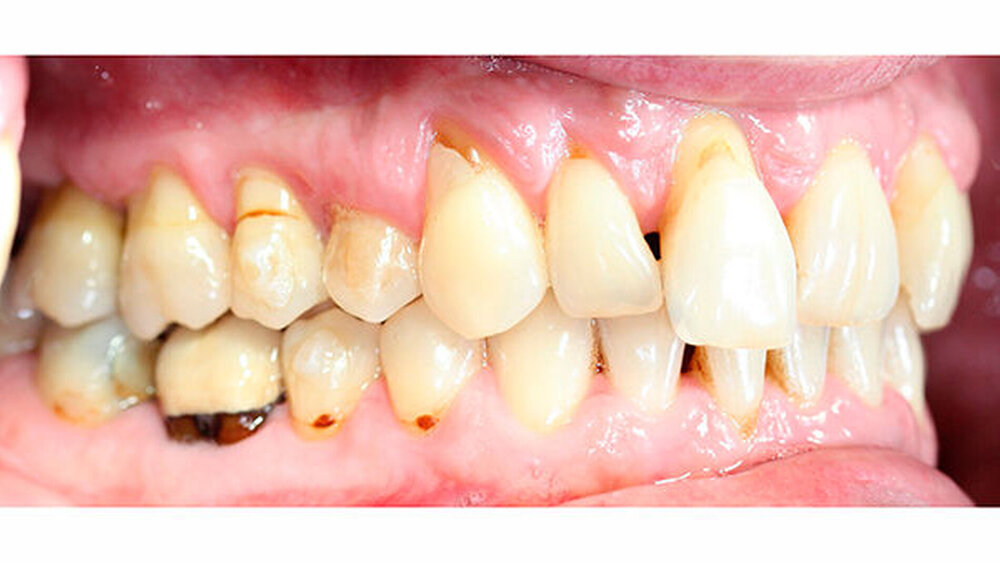

Intraoral zeigte sich ein bereits konservierend versorgtes permanentes Gebiss mit aktivem und inaktivem kariösen Geschehen. Große Anteile der Zahnhälse lagen nach Zahnfleischrückgang in Kombination mit Knocheneinbrüchen frei. Zahn 27 wurde bereits extrahiert.

Eine Beurteilung der parodontalen Situation an Zahn 11 offenbarte mesial und distal Sondierungstiefen von jeweils 6 mm.

Kieferorthopädisch imponierte beidseits eine neutrale Verzahnung bei einem tiefen Biss von 5 mm - bedingt durch die Verlängerung beider Frontzahngruppen. Besonders Zahn 11 zeigte eine erhebliche Verlängerung und Protrusion mit einer sagittalen Frontzahnstufe von 5 mm. Sowohl die Frontzähne im Ober- als auch im Unterkiefer wiesen eine lückige Beziehung zueinander auf (Abbildung 1).

Röntgenologisch stellte sich im Orthopantomogramm der bereits intraoral ersichtliche horizontale und vertikale Knochenabbau mit Attachmentverlust an einzelnen Zähnen dar. Die Erhaltungswürdigkeit einzelner Zähne war aufgrund des starken Knochenverlustes beziehungsweise der Beeinträchtigung des Halteapparates als kritisch zu beurteilen.

Zudem wurde die Diagnose einer Parodontitis gestellt, die eine Rücküberweisung an den Hauszahnarzt erforderlich machte (Abbildung 2).